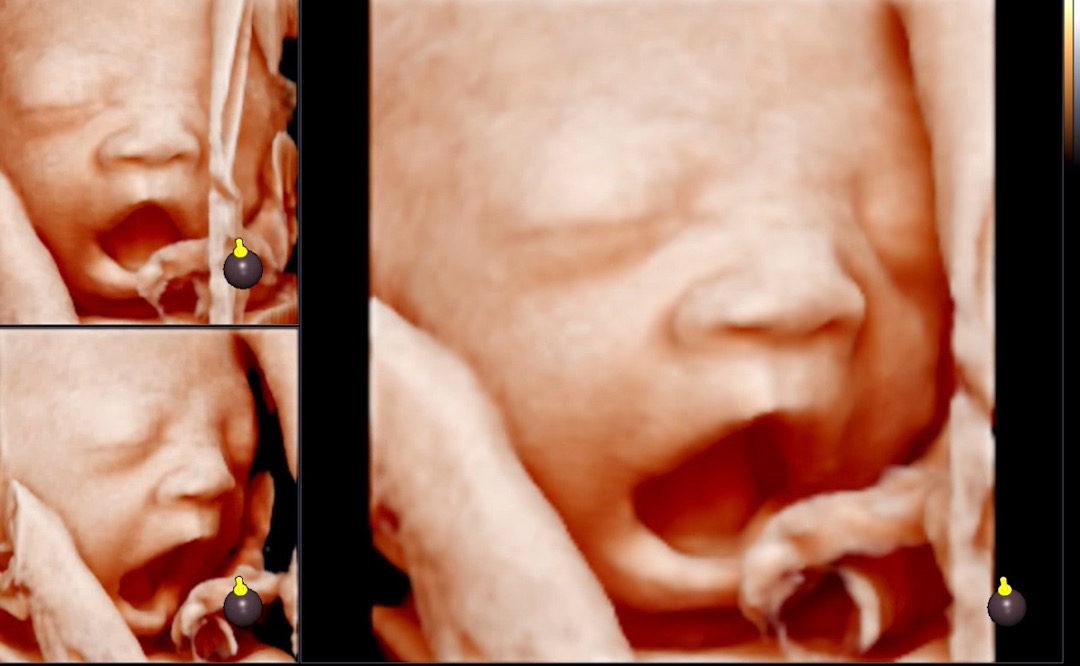

29주 입체초음파 보고왔어요

오늘 입체초음파보고왔어요~ 까꿍이가 하품하는거도 봤는데 으앙너무 귀여워요..♡ 넘귀여워서 보면서 눈물 찔끔났어요! 가기전에 단거 먹어야 잘움직인데서 초코 우유마시면서 병원이 5분거리라 천천히 걸어갔는데 아가가 손을 계속 입에대고 있고 탯줄에 얼굴이 가려져서 한참보다가 왔네요!ㅎㅎㅎ 그런데 아기가 주수에 비해 머리가 2주 크고 팔다리도 2주크구 전체적으로 2주크다고 하네요~! 담당 의사선생님께서는 우선 크는거 지켜보자구 하셨는데 자연분만하고싶은데 가능하겠죠..!!??